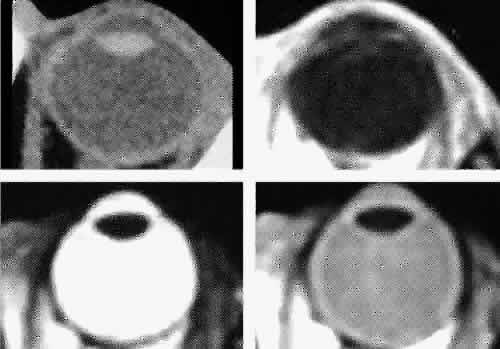

images.1,43–47 The globe is shown in Figure 12. The orbit and periorbital structures are shown in Figures 13 through 16, and the optic canal is shown in Figures 17 through 26. The cavernous sinus and optic chiasm are shown in Figures 27 and 28, and the posterior visual pathway and cranial nerves are shown in Figures 29 through 33.  Fig. 12. Axial cuts through the eye. Computed tomography (upper left), T1-weighted

magnetic resonance imaging (upper right), T2-weighted magnetic resonance

imaging (lower left), proton-density magnetic resonance imaging (lower

right). Fig. 12. Axial cuts through the eye. Computed tomography (upper left), T1-weighted

magnetic resonance imaging (upper right), T2-weighted magnetic resonance

imaging (lower left), proton-density magnetic resonance imaging (lower

right).

GLOBE Both MRI and CT are limited in their ability to image clearly the normal

intraocular structures (see Fig. 12). For the most part this is due to the small size and ultrastructural

composition of these structures. The cornea and sclera cannot be differentiated

from each other but are quite distinct on both MRI and CT owing

to their contrast with both the vitreous and aqueous internally and

the orbital fat and, if present, air trapped behind the eyelids externally. The

only other readily visible intraocular structure is the lens. On

CT this appears uniformly dense and similar in appearance to the

sclera. However, on T1-weighted MRI, the external lens capsule can be

clearly differentiated from the internal lens structure owing to the

presence of a significant number of hydrogen proteins within the central

portion of the lens. In addition, the normal choroid, ciliary body, and

iris can occasionally be visualized on MRI but not on CT. The normal

retina cannot be seen by either technique; neither can the conjunctive, Tenon's

capsule, angle structures, or the vessels and nerves

penetrating the globe. ORBIT AND PERIORBITAL STRUCTURES The bony orbital and periorbital anatomy is best visualized with CT, whereas